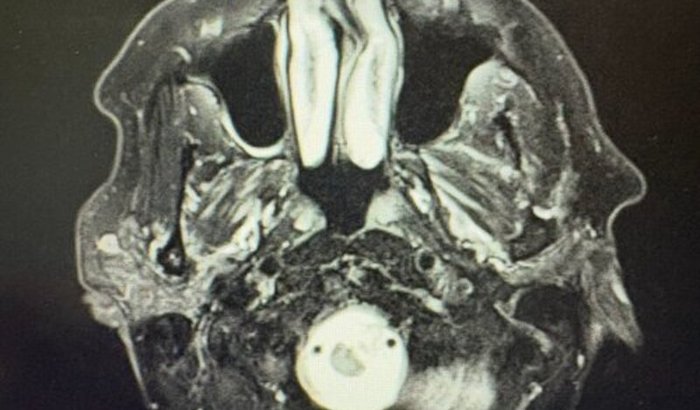

Recentemente, ele começou a sentir tonturas e, descobrimos em exame de rotina, que ele está com um tumor em sua cabeça, perto do tronco cerebral.

Apesar de ser benigno até o momento, está crescendo e pode causar paralisia e perda de sensibilidade por todo seu corpo.

O tumor meningioma está localizado em uma área de difícil acesso e a cirurgia convencional de extração possui um risco muito alto.